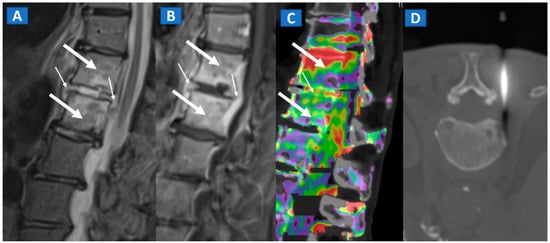

DECT has been successfully used to diagnose OCL of the knee and ankle both in traumatic and non-traumatic settings [3,7]. Painful OCL are typically associated with BME (Figure 3), often appearing as markedly edematous subchondral areas in DECT images, surrounded by milder and peripherally degrading BME [3,7]. However, some OCL can be missed by DECT, especially in the presence of subchondral sclerosis [8]. The analysis of additional associated findings, such as articular space narrowing that is typical of patients with osteoarthritis or meniscal or ligamentous injuries, may help in the identification of smaller, less obvious BME foci (Figure 4). In such cases, color-coding spared bone in violet and BME in shades of green, and correctly adjusting the level of superimposed BME information are key to an accurate diagnosis.

Figure 3.

A 48-year-old male with OCL of the talar dome and distal tibia. On the sagittal STIR MRI image (A), subchondral marrow lesions, associated with thinning articular cartilage, are depicted on the talar dome and distal tibia (arrow). On the corresponding sagittal 1 mm DECT map (B), BME is depicted in red (arrow), whereas normal bone is shown in shades of green-yellow. On the sagittal 1 mm reconstructed CT image with a soft tissue window (C), it is possible to identify an astragalic beak, subchondral sclerosis and articular space narrowing (arrow) as being the probable causes of non-traumatic BME.

Figure 4.

A 65-year-old female with non-traumatic medial-sided knee pain. On the coronal STIR MRI image (A) the body of the medial meniscus is ruptured and medially dislocated (thick arrow). Tiny, subtle BME areas can be seen on the femoral condyle (thin arrow) due to advanced chondropathy. Tiny areas of BME (thin arrow) are also depicted on the corresponding coronal 1 mm reconstructed DECT image (B). By using alternative color-coding (C), DECT allows the depiction of the ruptured meniscus (thick arrow), providing a good correlation with MRI findings.